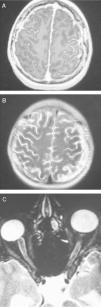

RM craneal, corte axial. Engrosamiento leptomeníngeo principalmente en el hemisferio derecho, con áreas más extensas frontal y parietal, y mínimo engrosamiento en la región frontal izquierda, que se realza con gadolinio (A) y brilla en secuencia FLAIR (B). RM canal espinal. Realce de la leptomeninge perimedular y del tronco del encéfalo (C y D).

Niño de 12 años con episodios en los últimos 2 meses de cefalea frontotemporal, vómitos biliosos matutinos, sensación de mareo, visión borrosa y parestesias en el hemicuerpo izquierdo. Presentaba un nevus pigmentado piloso gigante en el tercio superior de espalda y la nuca de 21 x 25cm y múltiples nevus de pequeño tamaño en los glúteos, el costado y el muslo derecho, que habían sido sometidos a múltiples intervenciones de extirpación y laserterapia de CO2. La exploración neurológica fue normal, salvo papiledema bilateral más intenso en ojo derecho. La tomografía computarizada craneal fue normal. La RM craneal mostró: engrosamiento leptomeníngeo de predominio en la región frontal y parietal del hemisferio derecho, con brillo en la secuencia FLAIR e intenso realce con gadolinio (fig. 1A y B). RM medular: realce de la leptomeninge perimedular y del tronco del encéfalo (fig. 1C y D). Punción lumbar: leucocitosis (25 cel/mm3), hipoglucorraquia (0,21g/l) e hiperproteinorraquia (0,63g/l); cultivos y serologías de virus y bacterias neurotropas, y citología de células malignas negativos. A los 7 días se repitió la punción lumbar encontrándose de nuevo hipoglucorraquia (0,21g/l), hiperproteinorraquia (1,05g/l) y una hipercelularidad (23 cel/mm3) con células mononucleares atípicas y aisladas células con pigmento pardo intracitoplasmático. A los 3 meses del inicio del cuadro neurológico presentó hidrocefalia tetraventricular que precisó derivación ventriculoperitoneal. La biopsia de meninges no evidenció lesiones histopatológicas. Pasado un mes el paciente sufrió pérdida de visión del ojo derecho y crisis convulsivas consistentes en desviación de la comisura bucal e hipertonía. La RM evidenció una extensa afectación leptomeníngea, afectando también a los pares craneales, incluido el quiasma óptico y los nervios ópticos en su porción intracraneal (fig. 2). A los 8 meses del diagnóstico el paciente presentó un deterioro neurocognitivo importante, con comportamientos regresivos, disminución de la capacidad de concentración, bradipsiquia y actitud reiterativa. Dos meses después una nueva biopsia objetivó proliferación melanocítica de localización perivascular que no infiltraba parénquima cerebral. Evolucionó desfavorablemente con empeoramiento hasta situación de coma y defunción a los 11 meses del diagnóstico.